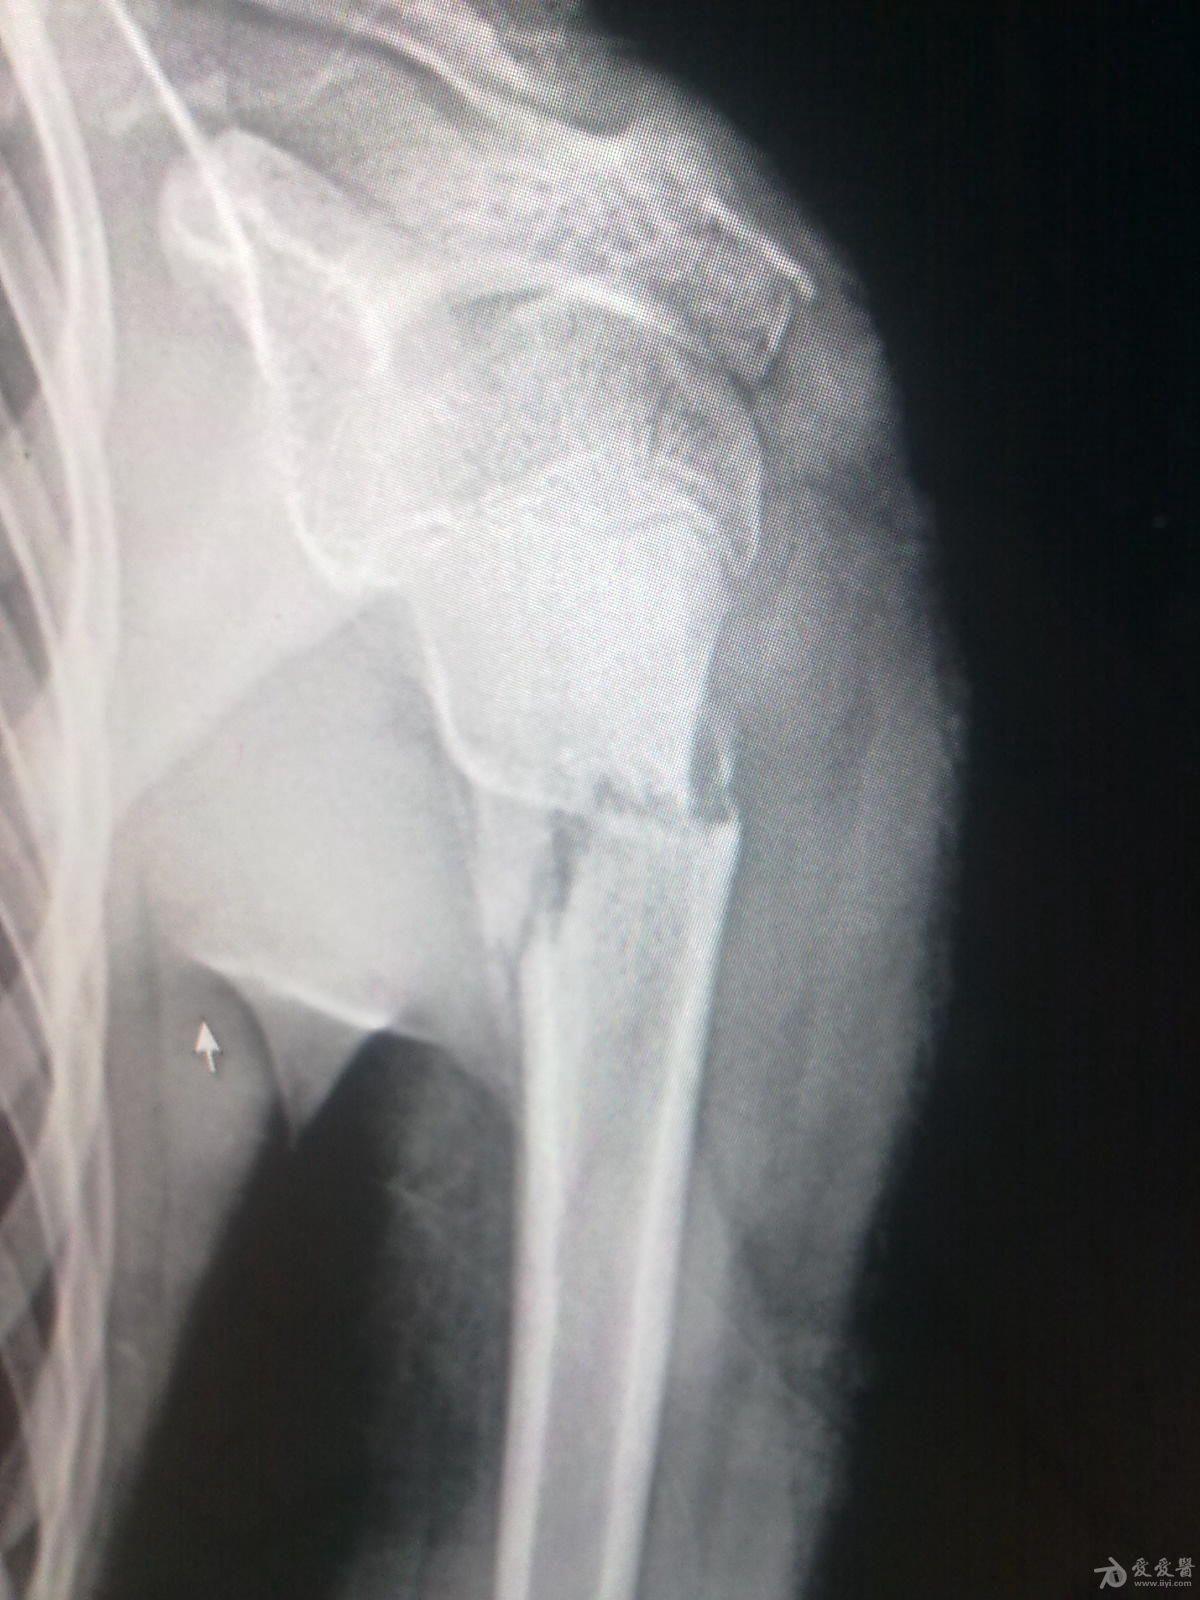

肱骨近端骨折斜位成角角度预后会不会塑形成功

图片尺寸1200x1600